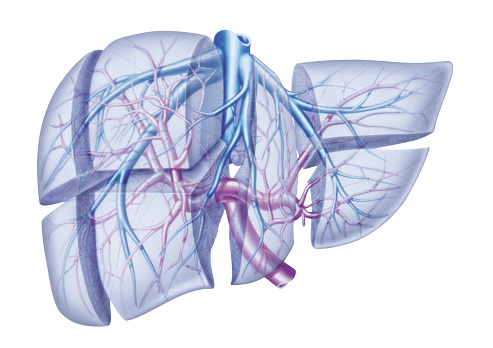

Cos’è il tumore del dotto biliare o colangiocarcinoma? Si tratta di una neoplasia abbastanza rara che ha origine da un dotto biliare. Questo è uno dei fisiologici tubicini che hanno il compito di spostare la bile dal fegato e dalla cistifellea fino al piccolo intestino, affinché qui possano essere digeriti meglio i grassi assunti con l’alimentazione. A seconda del punto in cui si trovano si chiamano in maniera diversa e sviluppano diverse forme di tumore.

bile